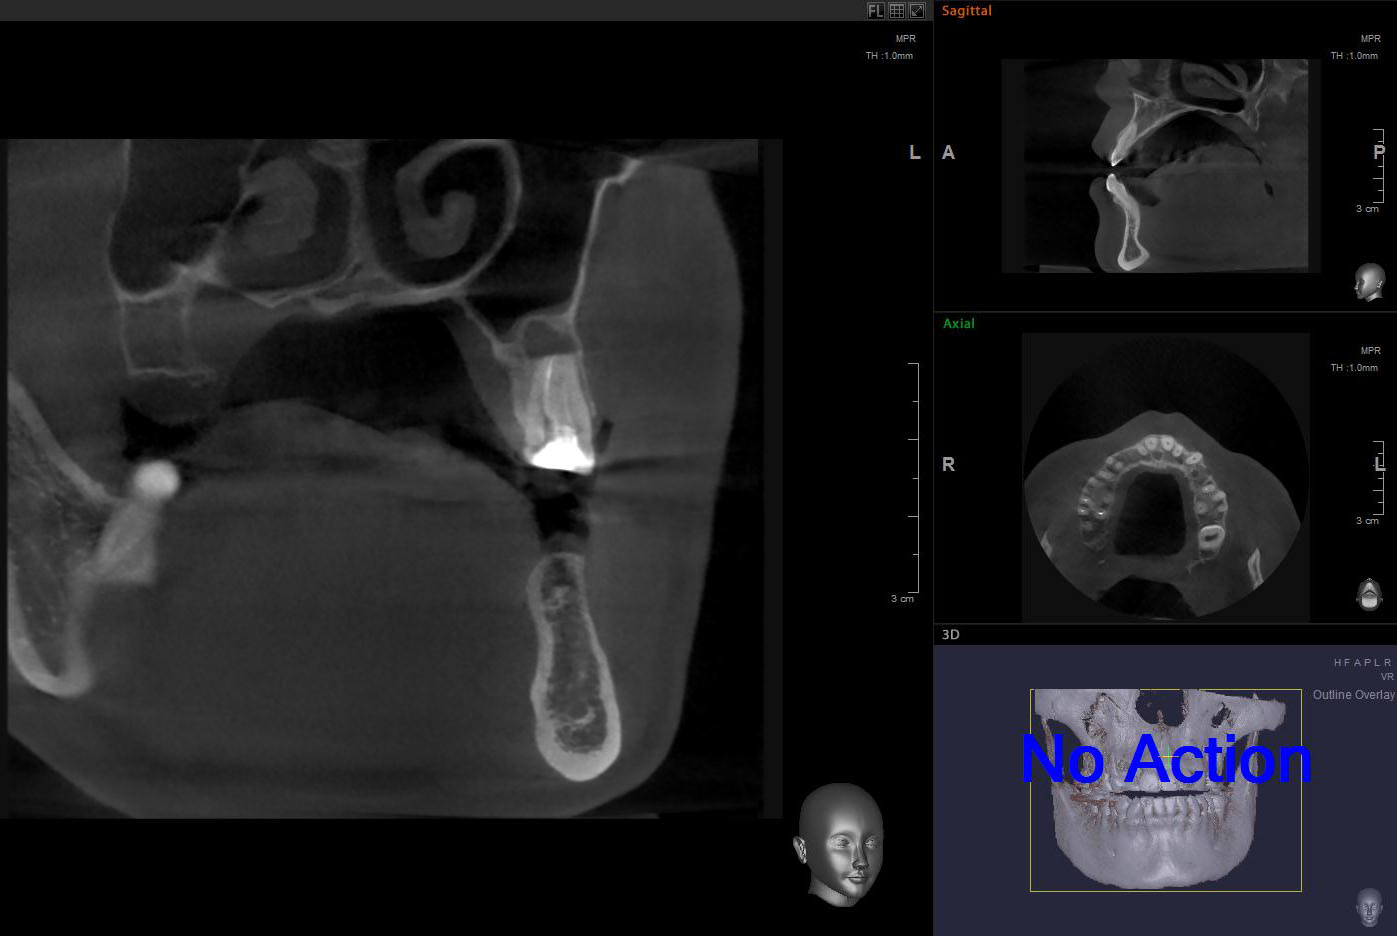

Для примера, давайте рассмотрим вот этот снимок:

Возможна ли имплантация в области левого верхнего премоляра? Вполне. Зуб и гранулему можно удалить, сделать синуслифтинг, вопрос со стабилизацией импланта решить по ходу операции. Остается только один вопрос:

— зачем усложнять?

Другой вариант лечения: удаление зуба, аугментация лунки, через полтора месяца можно приступать к имплантации. Без всяких синуслифтингов и проблем, связанных со стабилизацией импланта. Атрофия альвеолярного гребня? Эта проблема решается на этапе аугментации лунки.